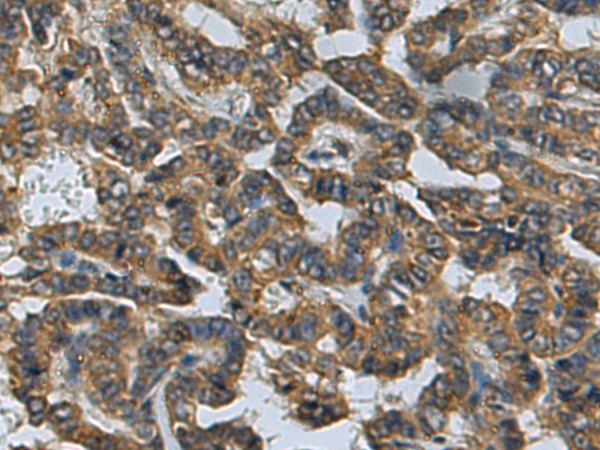

分类: 科研抗体货号: P09329别名: UBP; SIH003应用: IHC反应种属: Human, Mouse